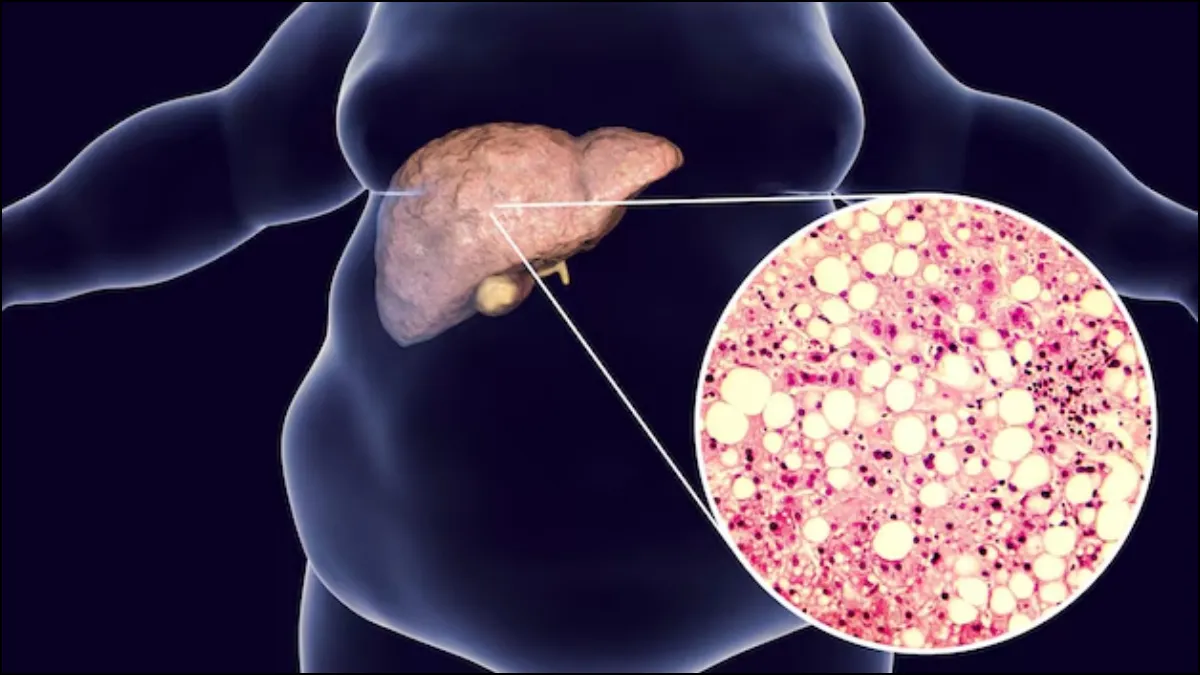

लिवर शरीर में रासायनिक कारखाने की तरह काम करता है जो पोषक तत्वों को तोड़ता है और खून में पाए जाने वाले विषाक्त पदार्थों को छानकर बाहर निकालने का काम करता है। लेकिन कुछ चीजें लिवर की सेहत के लिए बिल्कुल अच्छी नहीं मानी जाती हैं। जिसमें तेल, घी और चिकनाई सबसे ऊपर है, हालांकि चीनी भी लिवर को बहुत नुकसान पहुंचाती है। इससे फैटी लिवर और लिवर सिरोसिस का खतरा बढ़ता है। आइये जानते हैं मीठी चीजें लिवर पर क्या असर डालती हैं। लिवर चीनी और ग्लूकोज को कैसे पचाता है और ज्यादा मीठा खाने से लिवर पर क्या असर होता है?

लिवर में फैट- जब लिवर में ग्लूकोज की मात्रा बढ़ जाती है तो ये फैट में परिवर्तित हो जाता है, ये फैट लिवर कोशिकाओं में जमा होने लगता है। इससे लंबे समय में नॉन-अल्कोहल फैटी लिवर रोग का खतरा बढ़ जाता है। लिवर में फैट बढ़ने से लिवर में सूजन आने लगती है।

लिवर में सूजन और घाव- ज्यादा चीनी का सेवन करने से लंबे समय में लिवर में सूजन हो सकती है, कई बार तो लिवर में घाव (फाइब्रोसिस) हो सकता है। गंभीर मामलों में लिवर सिरोसिस हो सकता है।